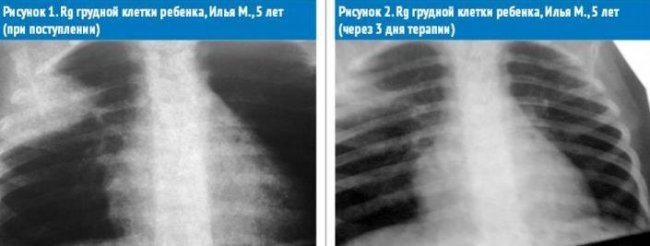

Илья М. 5 лет находился в инфекционном отделении ТДГБ (Москва) с диагнозом «Острая правосторонняя верхнедолевая пневмония. Острый обструктивный бронхит, средне-тяжелое течение». ДН 1-11. В стационар доставлен бригадой скорой помощи с жалобами на лихорадку, затрудненное дыхание.

Определяется инфильтративная тень в области верхней доли правого легкого. Легочный сосудистый рисунок обогащен с обеих сторон с выраженным интерстициальным компонентом.

Поставлен предварительный диагноз: Острое респираторное заболевание. Обструктивный бронхит, средне-тяжелое течение. ДН11. Правосторонняя пневмония.

При серологическом исследовании сыворотки крови были выявлены антитела класса М к Mikoplasma Pneumonia, превышающие допустимую норму (1:400).

Наличие инфильтративной тени в области верхней доли правого легкого и лабораторно выявленная микоплазменная инфекция, позволили предположить участие в этиологии данного заболевания смешанной кокковой и микоплазменной флоры.

Через 3 дня терапии отмечалась положительная рентгенологическая динамика. Уменьшение интенсивности и размера инфильтрата. Сохраняется обогащение, сосудистый рисунок обогащен с обеих сторон.

Данный клинический случай интересен тем, что ОРЗ смешанной этиологии – бактериально-микоплазменной, изначально имеющее клинику острой респираторной вирусной инфекции, со всеми характерными симптомами (субфебрильная лихорадка, ринит, покашливание) в дальнейшем (на 9-е сут. от начала заболевания) привело к развитию осложнения в виде острой бронхиальной обструкции и пневмонии. Данные клинического осмотра, дополненные лабораторными (лейкоцитоз в общем анализе крови, положительные титры антител к микоплазменной инфекции при серологическом исследовании) и инструментальными исследованиями (инфильтративные изменения в легких больше характерные для кокковой флоры, на фоне усиление интерстициального рисунка легких, которое характерно для микоплазменной инфекции) позволили поставить полный диагноз «Острое респираторное заболевание вирусно-бактериально-микоплазменной этиологии. Правосторонняя верхнедолевая пневмония. Обструктивный бронхит, средне-тяжелое течение». Назначенная этиопатогенетическая терапия способствовала быстрому выздоровлению.